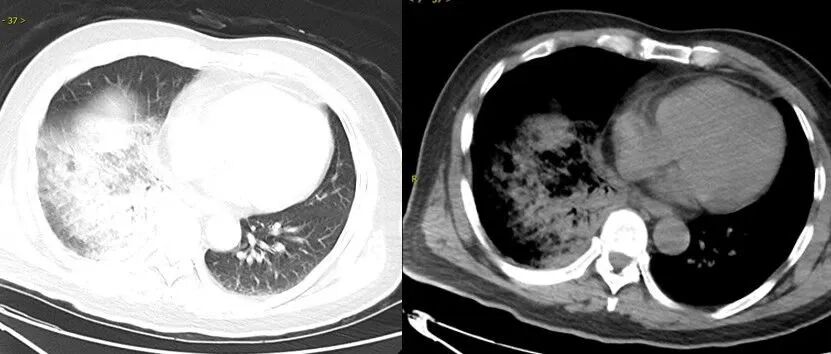

鹦鹉热衣原体肺炎影像示例。图源:江苏省人民医院